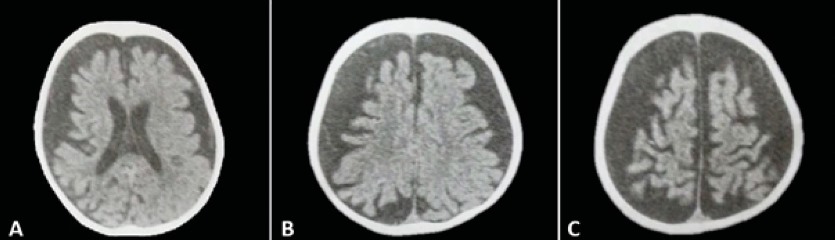

Se han visto sin embargo múltiples hallazgos radiológicos como ser atrofia de lóbulos cerebrales, hipertrofia de plexos coroideos, agrandamiento de las venas cerebrales profundas, anomalías de drenaje venoso y recientemente se ha descrito un agrandamiento asimétrico del seno cavernoso 4, 24 ( Figura 3).

Fuente:elaboración propia.

Las pruebas de imágenes, como ecografía doppler, tomografía computarizada (TC) o imágenes por resonancia magnética (RM), pueden ser útiles para determinar cualquier posible malformación vascular localizada en tejidos profundos, por ejemplo, malformaciones vasculares cerebrales o malformaciones arteriovenosas 4, 11. La técnica de neuroimagen de elección para el diagnóstico de SSW actualmente es la resonancia magnética con contraste de gadolinio, ya que puede demostrar la presencia de angiomatosis leptomeníngea y determinar el grado de afectación de las estructuras del cerebro 4.